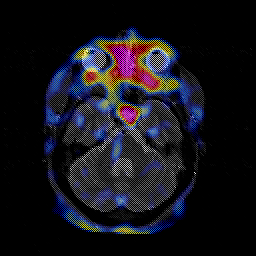

Glioblastoma multiforme overlay -- Slice #17

[Home][Help][Clinical][Tour 1][Tour 2][Tour 3] Slice 17